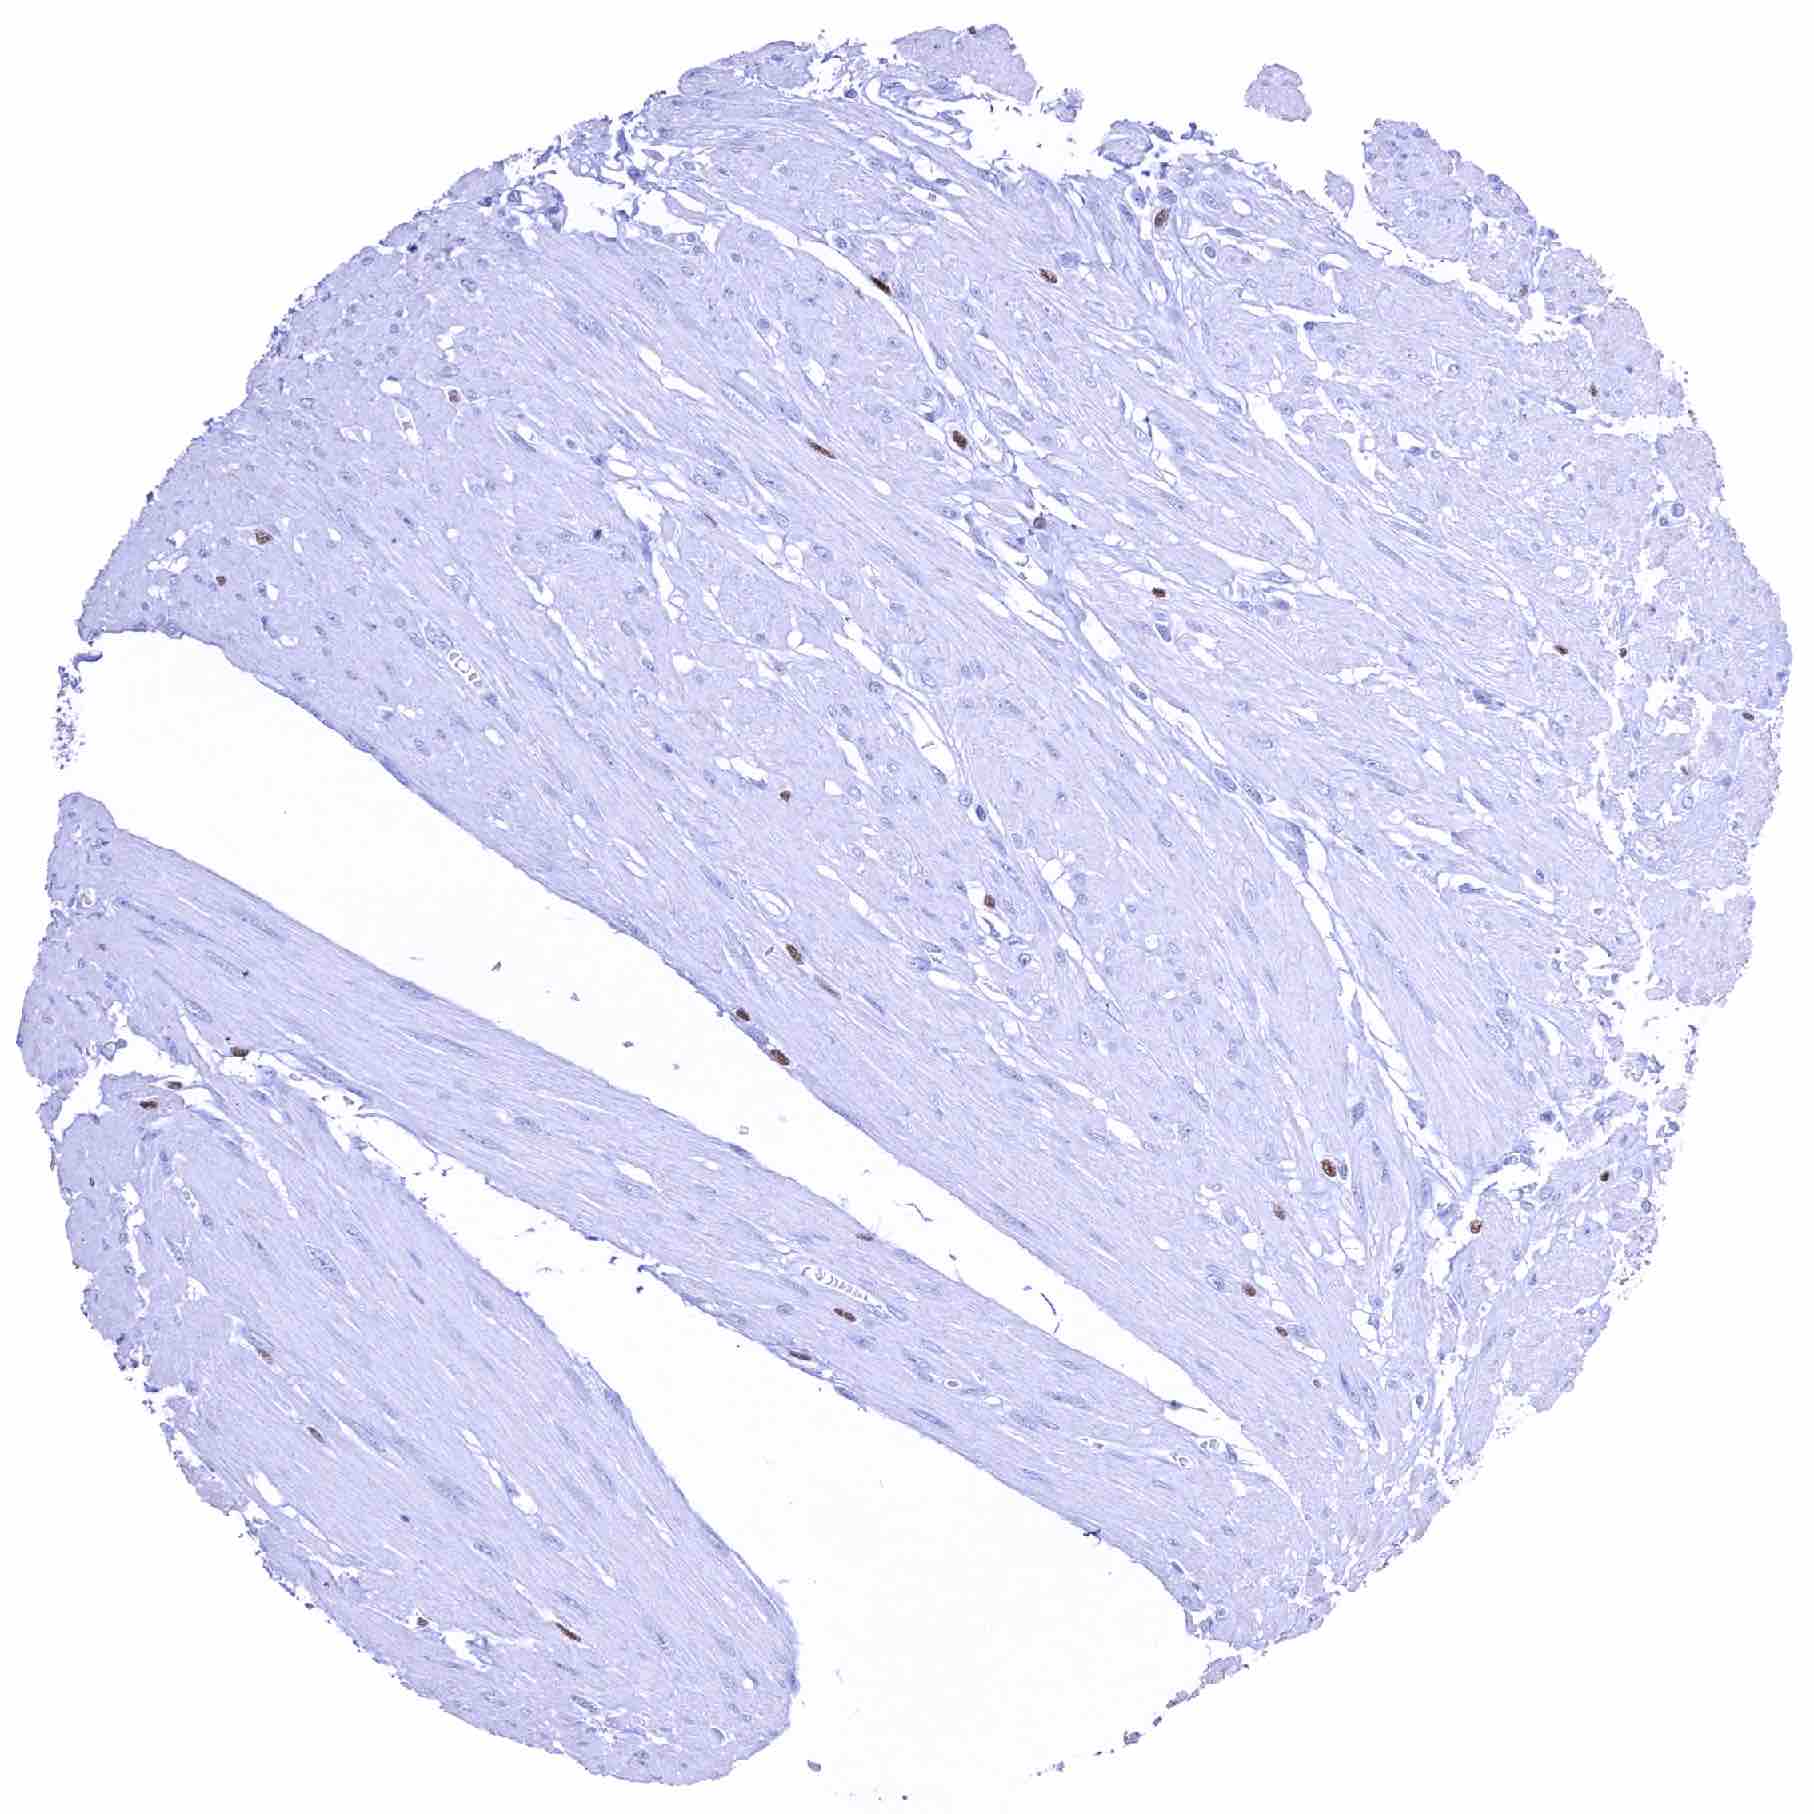

Urinary bladder, muscular wall